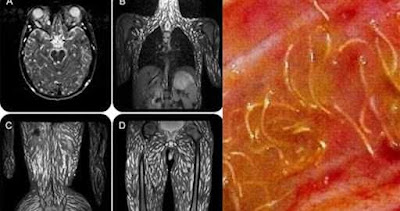

一名泰國18歲男子日前因為頭痛、抽搐、嘔吐、感官扭曲等症狀就醫,醫生透過核磁共振發現,男子的大腦組織、胸腹腔、肚子、四肢竟長滿豬肉絛蟲,畫面驚悚。醫生推測,他應該是吃了上面有蟲卵的半生不熟豬肉所導致。

泰國《詩華日報》報導,這名男子經過核磁共振檢查後確診為豬囊蟲病。從照片上可以看到,男子的大腦組織、頭部、胸腹腔、脊椎甚至四肢,體內幾乎每個角落都有豬肉絛蟲在爬。醫生初步判斷,男子應該是吃了半生不熟的豬肉、或是有蟲卵的蔬菜、水果與水源導致,所幸經過驅蟲藥物、類固醇與抗癲癇藥物治療後,男子已經漸漸好轉。

在台灣,也曾發生過原住民生吃山豬肉導致腿生絛蟲的病例。據衛福部新聞稿,敏盛外科主治醫師陳太其指出,豬肉絛蟲是人畜共通的寄生蟲,成蟲會寄生在腸道、產卵,孵化的幼蟲會穿過腸壁進入腹腔亂跑,常寄生在橫紋肌,甚至竄到腦、眼、心臟。如竄入腦部可能引發水腦,重則死亡,穿入眼部會造成視網膜病變,重則眼瞎。豬肉絛蟲寄生於豬肉居多,也會寄生在牛、羊、鹿身上,所以肉類應煮熟再吃#豬肉半生不熟 #豬肉絛蟲 #寄生蟲 #男子 #大腦 #醫生 #養生 https://www.chinatimes.com/realtimenews/20200615001957-260405?chdtv